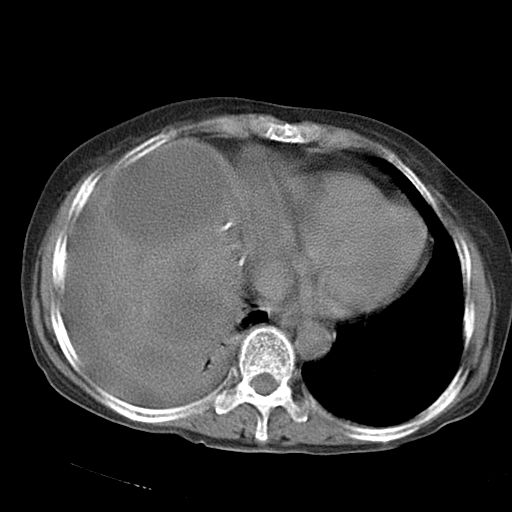

以下是引用dyqct在2006-12-7 21:08:00的发言:[br]考虑:1、肝内外胆管多发性结石伴肝左叶外侧段肝萎缩;[br] 2、右膈下多发脓肿;[br] 3、右侧少量胸腔积液、斜裂积液;[br] 4、左肾囊肿。

以下是引用jiazh在2006-12-7 20:37:00的发言:[br]肝脏周围半狐形低密度影,肝脏表面受压推移,考虑膈下脓肿可能性大;2、右侧胸腔积液

以下是引用拾荒者在2006-12-7 21:44:00的发言:[br]肝内外胆管多发结石,右膈下多发脓肿,右胸膜腔及叶间裂积液,左肾囊肿。[br] [br]